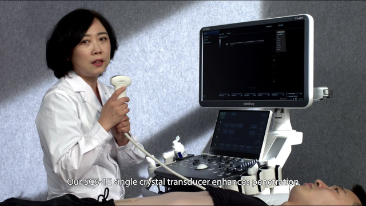

Allgemeine Bildgebung

Mit den allgemeinen Bildgebungsl?sungen der Resona-Serie von Mindray k?nnen Arzt und ?rztin genauer und effizienter diagnostizieren sowie bessere Behandlungserfolge erzielen, durch umfassende geteilte Anwendung der Sonden und effiziente klinische Anwendungstools.